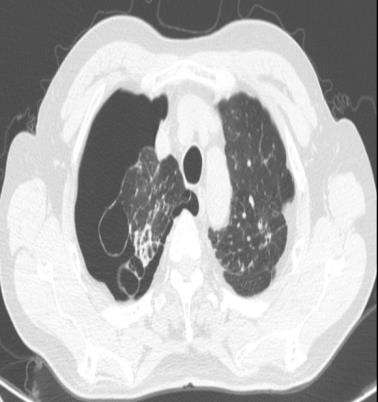

• 右肺中叶病变的临床特征分析(附709例报告)

2026, 32(3):45-50. DOI: 10.12235/E20250294

摘要 (42) HTML (59) PDF 1.50 M (41) 评论 (0) 收藏

摘要:目的 探讨右肺中叶支气管异常患者的人口学特征、临床表现、病因、影像学表现和支气管镜下表现。方法 回顾性分析2015年5月-2025年4月于该院在支气管镜检查中表现为右肺中叶异常改变的709例患者的临床资料,统计分析病因和临床特征。结果 709例患者中,男465例,女244例。男患者年龄(63.1±9.1)岁,明显高于女患者的年龄(60.9±11.5)岁,差异有统计学意义(P < 0.05)。临床表现主要包括:咳嗽、气促、咯血、痰中带血和胸痛,9.9%的患者未出现临床症状。根据年龄范围进行分组,将年龄 > 55岁的542例(76.4%)患者纳入高龄组,≤55岁的167例(23.6%)患者纳入低龄组,高龄患者明显多于低龄患者,差异有统计学意义(P < 0.05)。高龄组中,常见的3种病因分别为:肿瘤、炎症和结核。支气管镜下表现为:右中叶新生物、黏膜肥厚或肿胀、管腔狭窄和瘢痕闭塞等。结论 右肺中叶病变的患者采用影像学和支气管镜相结合的方式,对明确病因和指导临床治疗有重要意义。